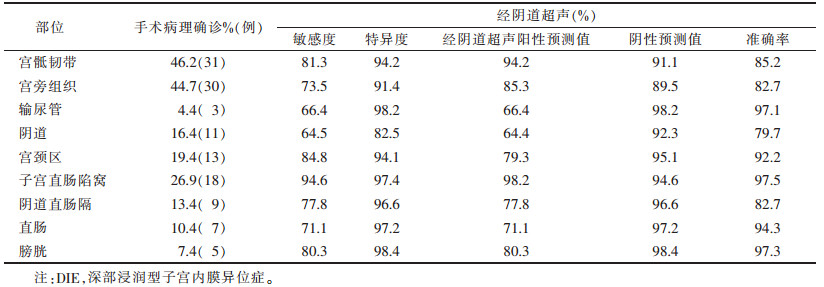

超声共发现病灶区101个(图 1~4),敏感度79.5%,超声诊断与手术结果对照见表 1。经阴道超声诊断的最低敏感度(64.4%)和准确率(79.7%)在阴道,最高敏感度(94.6%)和准确率(97.5%)在直肠子宫陷凹。

| 表 1 不同部位DIE病灶经阴道超声与手术病理结果对照 |